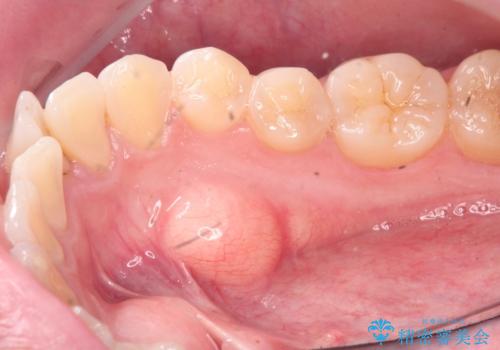

マウスピース矯正前に行う骨隆起の除去

- マウスピース矯正を行うにあたり、舌のスペースが狭くなってしまうことから骨隆起の除去を希望されました。

骨隆起の除去は30分ほどの小手術で終了します。